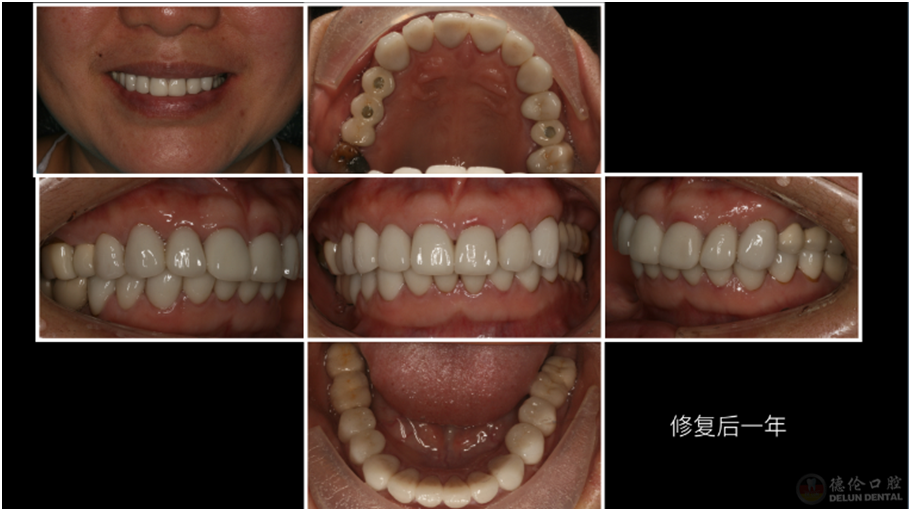

治疗方法:治疗牙髓炎和根尖周炎的患牙、拔除残根残冠、升高咬合,种植修复及全冠修复。

术后: